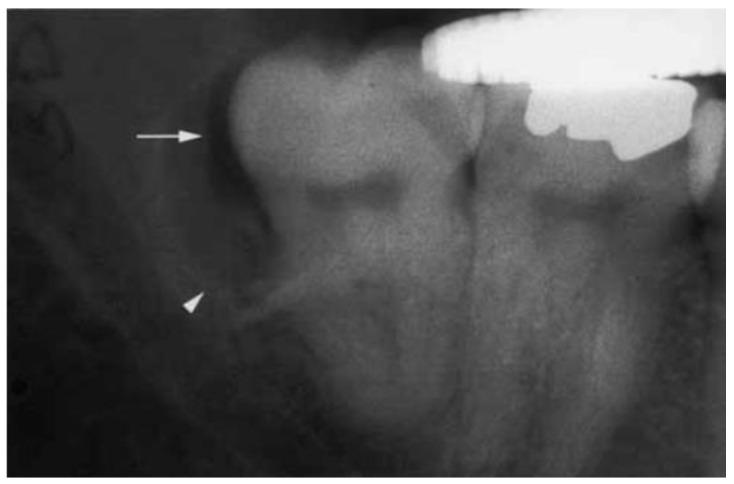

Paradental cyst (PC) is an uncommon type of odontogenic cyst of inflammatory origin, which develops near the cervical margin of the outside of the root of a vital tooth. The category of paradental cyst includes the buccal bifurcation cyst, which is found in the buccal area adjacent to the mandibular first or second molars in children. A conclusive diagnosis of a PC needs to correlate the surgical, radiographic, and histologic findings. When strict diagnosis is neglected, they can be easily misdiagnosed and mistreated. PCs associated with mandibular first and second molars and those associated with the mandibular third molar may have slightly different clinical manifestations but have almost completely different treatment principles due to the distinction in location. For the third molars, removal of both the tooth and the cyst is preferred. However, when the first or second molars are affected, it may be advisable to perform enucleation of the lesion while preserving the associated tooth. There are also more conservative methods to retain vital permanent teeth within the mandibular arch. Additionally, the cyst wall primarily consisted of granulation tissue firmly attached to the periodontal ligament space. The exact origin of these cysts was a subject of ongoing debate, but they were believed to primarily arise from either the reduced enamel epithelium or the inflammatory proliferation of junctional/sulcular epithelium, which originate from the superficial mucosa during tooth eruption. The aim of the present review was to update information on clinical manifestations, diagnosis and treatment strategies of cysts and discuss their pathogenic mechanisms. Raising familiarity with the distinctive features is beneficial for accurately diagnosing these lesions and effectively caring for the patients.